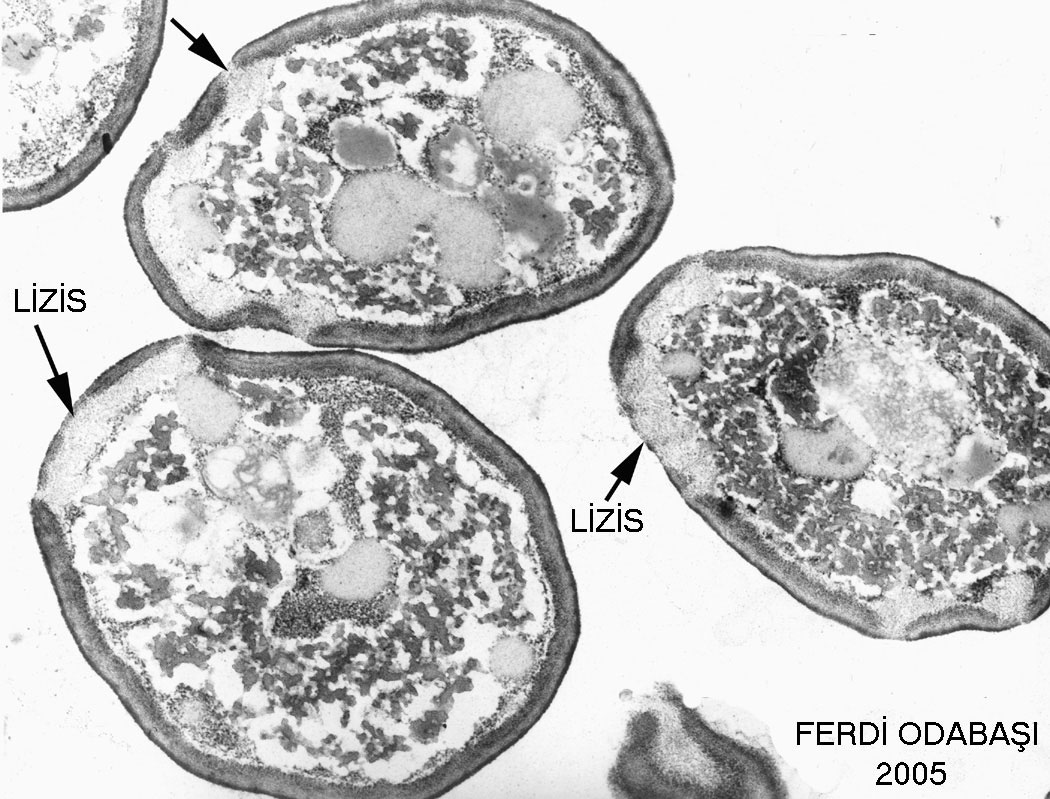

u/Lizis.jpg